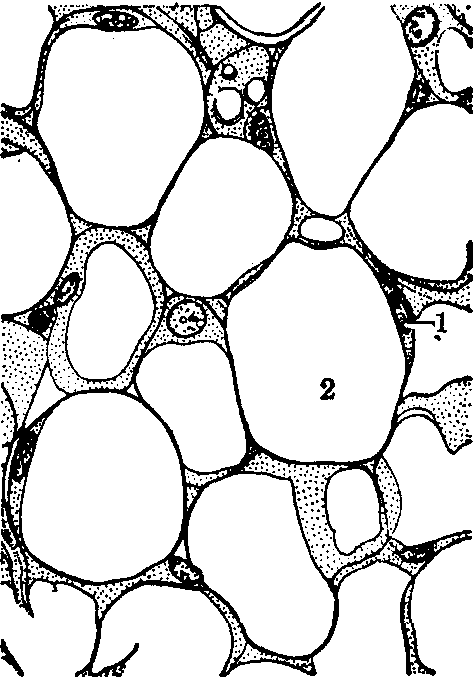

白(黄)脂肪组织 通常所谓的脂肪组织即指此型而言,也称普通脂肪组织(见图)。它由大量单泡脂肪细胞聚集而成,故又称单泡脂肪组织。脂肪细胞中央有一大脂滴,胞质成薄层分布在细胞周缘,胞核扁圆形,位居细胞一侧(参见“脂肪细胞”条)。脂肪细胞周围有网状纤维支持。动脉由小叶间隔伸入脂肪小叶内,在脂肪细胞间形成毛细血管。交感神经节后纤维形成动脉周围丛,神经末梢不直接接触脂肪细胞。在普通脂肪组织中,脂肪占其重量的60~85%,水占5~30%,蛋白质占2~3%;脂肪中90~99%为甘油三酯,也含少量游离脂肪酸、甘油单酯、胆固醇、磷脂,及微量胆固醇酯和甘油二酯。此型脂肪组织的分布很广。在皮下组织内的脂肪组织,含量有明显的年龄和性别的差异,如婴幼儿成为厚度均匀的皮下脂肪层,而成年女子在乳房、臀部及股前方特别丰富。此外,在两性的网膜、系膜和腹膜后区均有广泛的脂肪组织聚集。

白(黄)脂肪组织

1.脂肪细胞核 2.脂滴